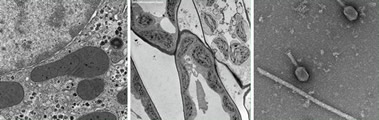

EMS公司自豪地推出一款無鈾染液,對TEM以及所有的染色應用而言,它是一種全新的比對染色試劑,可以取得和醋酸雙氧鈾一樣的實驗結果。

染色速度快(一分鐘),無輻射擔憂。有時候,為了增強比對效果,可以使用檸檬酸鉛負染。為了防止沉淀發生,使用室溫蒸餾水溶解染液。

Uranyless無鈾染液的PH值大約在6.8-7之間。壓力瓶(有噴嘴)保存,延長了保質期,減少了二氧化碳的污染。

無鈾染液可以應用在很多生物組織上,例如:腸、骨骼、心肌、肝臟、腎臟、神經、細胞培養、植物組織等,還有抗菌素、細菌和高分子材料。無鈾染液的穩定性和可重復性都表現的非常理想,圖片如下